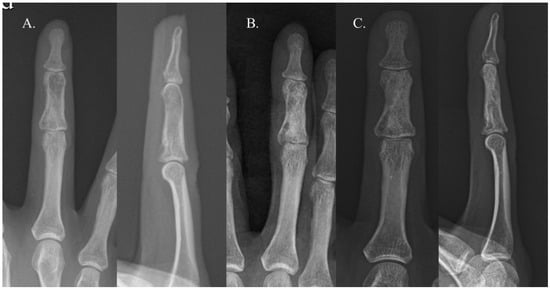

Recurrence occurred in only one case. The patient in question was a 22-year-old woman with an enchondroma in the middle phalanx of her left third finger. She underwent curettage and allogenic cancellous chip bone grafting. The bone graft filled approximately 39% of the defect, categorizing it as Group B (Figure 2). Sixteen years later, the enchondroma recurred in the same location. Repeated curettage and allogenic cancellous chip bone grafting were performed, and pathological analysis confirmed the presence of an enchondroma (Figure 3). There were no complications, such as infection, malunion, persistent pain, or refracture, in either group.

Figure 2. A 22-year-old female with an enchondroma in the middle phalanx of her left third finger. The images show simple radiographs taken before surgery (A), immediately after surgery (B), and 1 year after surgery (C). The bone graft filled approximately 39% of the defect, categorizing it as Group B.